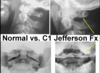

What type of fracture is seen on the radiograph? What featuers are you looking for?

Symmetry on either side of the dens

alignment of lateral masses

Jefferson fracture (radiogrph and CT)

atlas